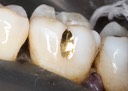

Frank Fukuda #19 buccal foil